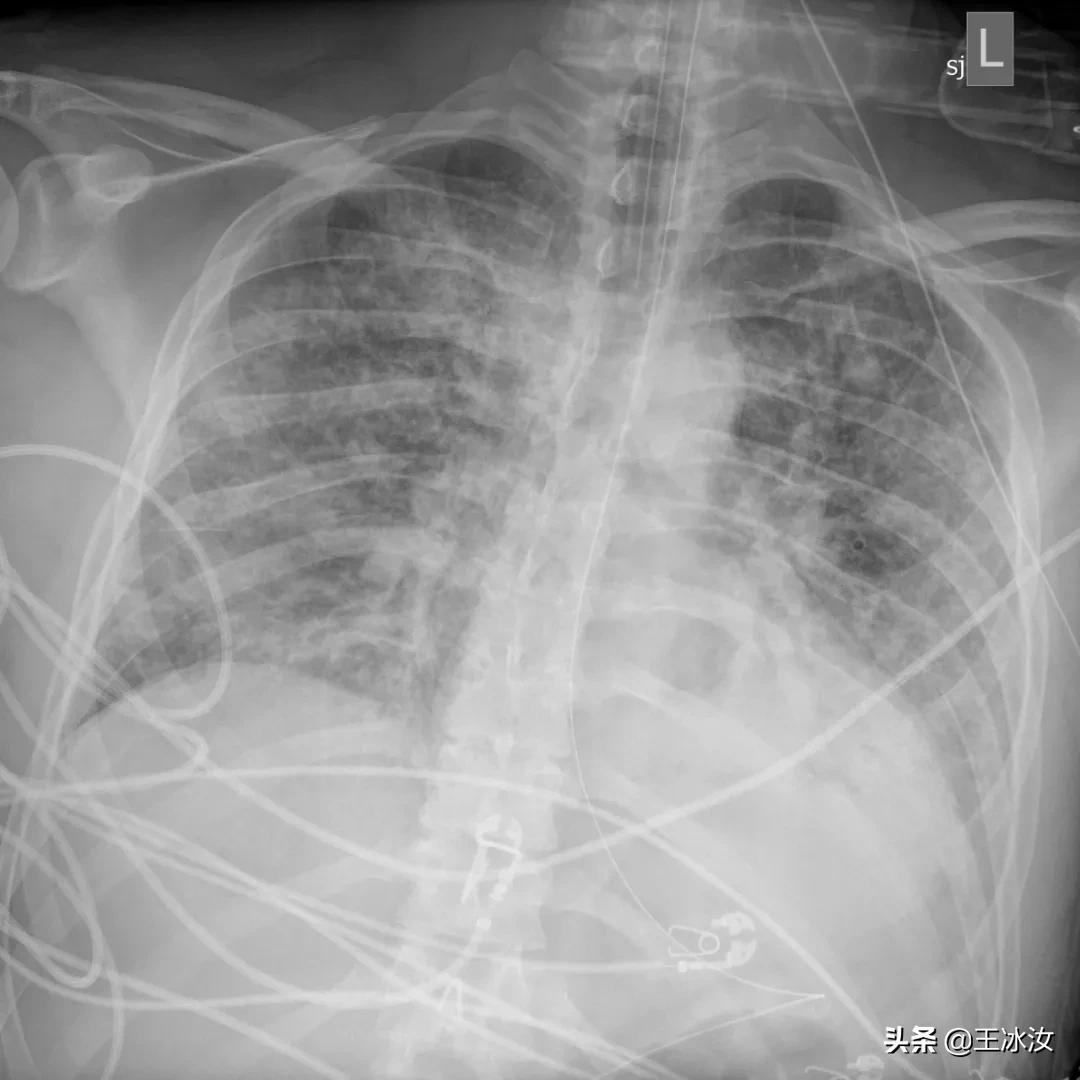

在胸部拍片检查中,他的肺部看起来和旁边的骨头一样白,整个肺部已经没有了含气的地方(肺内实变之后含气量减少,密度增高,颜色变白),他的医生库里尔(Paul Currier)说:“这是我见过最糟糕的胸部拍片”。

3月14日,贝洛的第一张肺部X光,肺部充满液体和炎性细胞

虽然医生已经放出了大绝招,但是贝洛胸片越来越糟。他第一次拍的胸片虽然显示出明显的积液和炎症,但还可以看出肺脏影像,3月18日,胸片所见恶化,但肺的轮廓仍然可见。到3月20日时,他的肺部表现基本上就是我们所说的“大白肺”(完全实变,肺影全部变白)